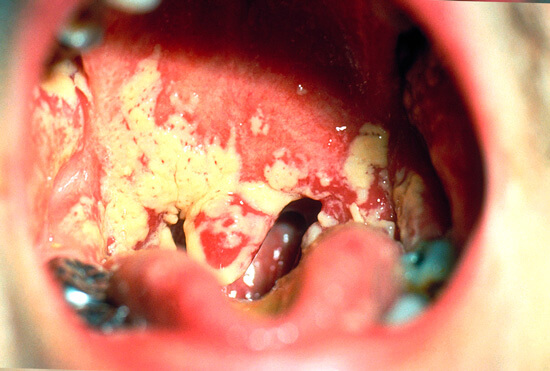

Для примера приведем фото типичной грибковой ангины:

Здесь в первую очередь вспомним, что грибковой ангиной в большинстве случаев ошибочно называют не воспаление миндалин, вызванное грибками, а поражение грибком всего глоточного кольца. Поэтому легче всего отличить грибковую ангину от бактериальной можно по тому, что при грибковой сам налет обычно имеется и на миндалинах, и на язычке, и на небе (в том числе и на небных дужках), а иногда — на языке, деснах и задней стенке горла. При бактериальной ангине гнойники локализуются только на миндалинах, хотя покраснение может распространяться на небные дужки и мягкое небо.

- Налет при грибковой ангине напоминает кусочки творога. Его так и называют — творожистые выделения, и из-за этого же в народе и грибковую ангину в том числе называют молочницей рта. Этот налет легко снимается ватой или пальцем, под ним не остается ран или язв. Напротив, гнойники при бактериальной ангине выглядят, как заполненные гноем резервуары, либо язвы. Для них характерно то, что они находятся внутри верхних слоев миндалин и как бы составляют часть их, в то время, как налет при грибковой ангине всегда появляется на поверхности. При бактериальной ангине гной удаляется уже с большим трудом, после чего на его месте остаются пятна свежей эпителиальной ткани без кровотечения;

- При грибковой ангине обычно значительно меньше выражено воспаление миндалин. Иногда они не увеличиваются в размерах и не краснеют вовсе, а лишь покрываются творожистым налетом;

- При грибковой ангине часто возникает воспаление только одной миндалины, что является редкостью для бактериального воспаления.